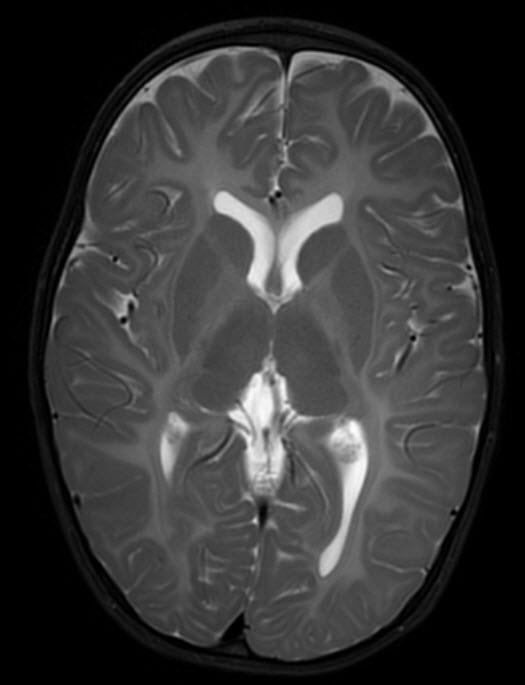

Canavan Disease Canavan Disease

• Diffuse, subcortical WM + globi pallidi / thalami (not putamina) Diffuse, subcortical WM + globi pallidi / thalami (not putamina)

• Spectroscopy: High NAA peak (diagnostic!) Spectroscopy: High NAA peak (diagnostic!)

• Mnemonic: Ca Mnemonic: CaNAANAAvan van